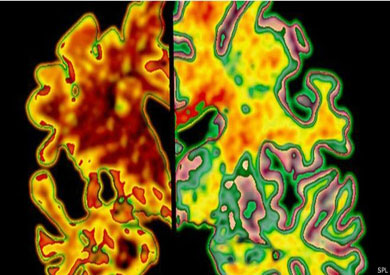

يعتقد علماء بأن العلاج بحقن مادة بروتينية طبيعية قد يخفف من اعراض مرض الخرف (الزهايمر) ويبطئ تطوره، وذلك بعد ان تكللت التجارب الاولية التي اجريت على الفئران بالنجاح.

وبينت نتائج الاختبارات ان الحقن ببروتين IL33 يحسن الذاكرة وويساعد في ازالة الترسبات المشابهة لتلك التي تشاهد عند مرضى الزهايمر او حتى منع تكونها بالمرة.

وسبق ان اكتشف ان المصابين بخرف الزهايمر لديهم كميات اقل من IL 33 مقارنة بالاصحاء.